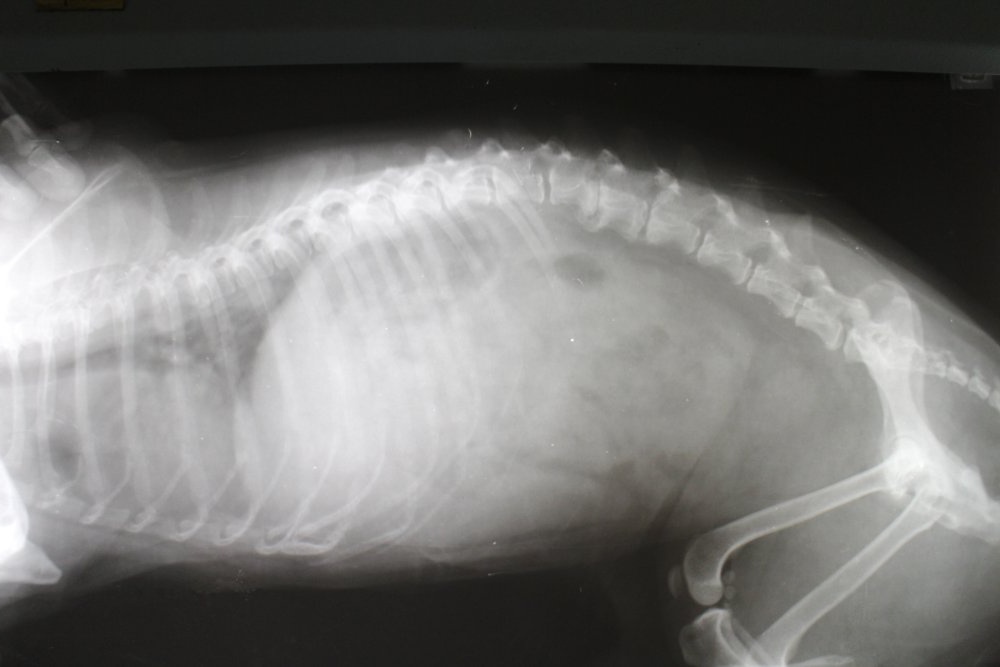

X-rays versus CT, MRI, and myelography

X-rays can help identify fractures, vertebral changes, and some patterns of disc mineralisation. However, they do not directly show the spinal cord, and they are not a reliable way to confirm or rule out IVDD on their own.

CT and MRI provide a much clearer view of the spine and the tissues around it. Myelography (a contrast study around the spinal cord) is sometimes used as well, especially in surgical planning. Your vet will talk you through what each test can and cannot answer in your dog’s case. 5, 6